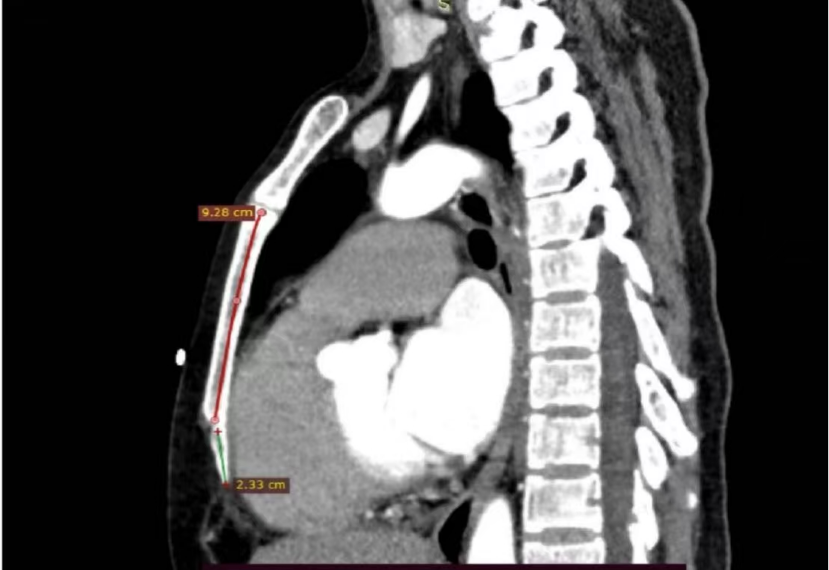

本例患者为47岁女性,因室速、室颤发作伴意识丧失,经外院电复律抢救后转入甘肃省人民医院。入院后心脏彩超提示心脏扩大,左室射血分数(LVEF)仅为38%,心脏核磁进一步提示结缔组织病变累及心肌。住院期间患者反复出现恶性心律失常,共接受7次电复律治疗,符合植入ICD的强适应证。

谢萍教授指出,EV-ICD技术是ICD领域的重要革新。其无静脉导线设计可有效解决静脉通路异常、闭塞或高感染风险患者的植入难题,兼具电池寿命长、功能集成度高等优势,为心脏性猝死高危人群提供了更精准、更可持续的个体化防治方案。此次手术中电极位置稳定,除颤阈值(DFT)测试一次达标,印证了该技术在临床实践中的安全性与有效性。